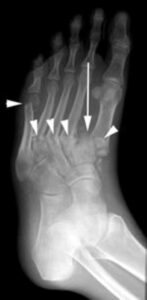

- X-rays: X-rays are a crucial diagnostic tool for Charcot foot. In the early stages, X-rays may appear normal. However, as the condition advances, signs such as fractures, bone fragments, and joint destruction become evident. Over time, more severe deformities, dislocations, and new bone formations may develop, indicating progressive Charcot arthropathy.

The patient shown in the X-ray had noticed swelling of the foot for approximately 3 weeks without any known injury. The X-ray shows several fractures (arrowheads) and a dislocation of the first metatarsal (arrow). Such a severe injury in patients without diabetes would be seen only after a high-energy trauma.